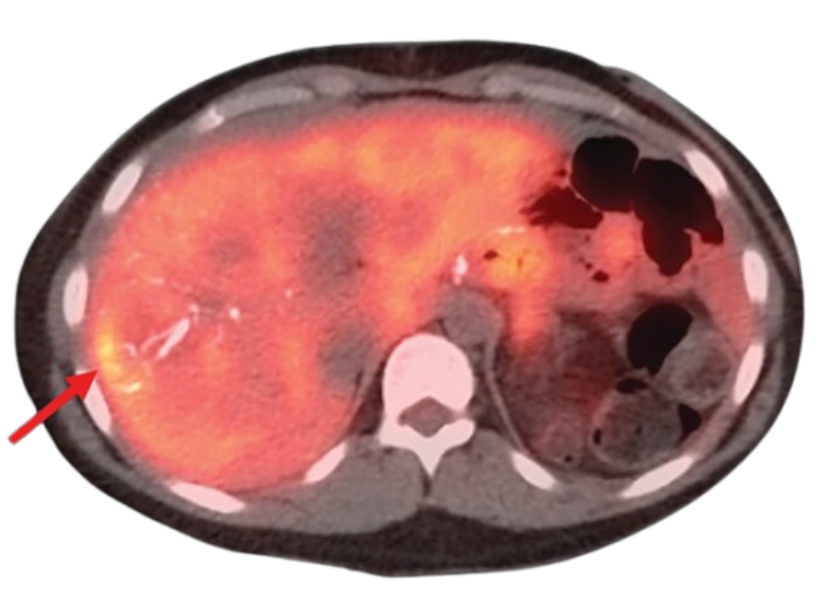

Neuroendocrine tumors often behave differently from other cancers, sometimes growing slowly while causing varied symptoms. Hormonal imbalances, digestive issues, or unexplained fatigue may be early indicators. Dr. Sasmita Vadgaonkar in Vile Parle offers tailored treatment for neuroendocrine tumors based on individual tumor characteristics.

Treatment depends on tumor type, location, and rate of growth. Surgical management may be combined with targeted therapies or medical treatment aimed at symptom control. Continuous monitoring plays a vital role in adapting treatment as the disease evolves.